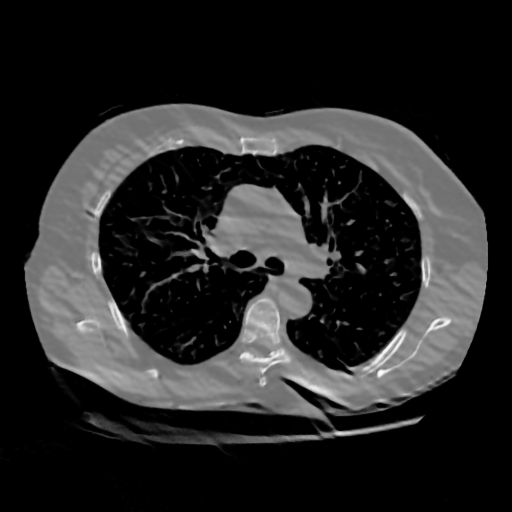

IV-C Few-View CT Reconstruction

In this section, the reconstruction performance of our proposed framework under few-view conditions will be tested. For the parallel and fan beam geometry, the number of views increases from to , uniformly distributing from to and to respectively. Such settings provide a complete benchmark of reconstruction performance, ranging from extremely sparse to relatively complete, full-view CT reconstruction. The experiment results are shown in Fig.5. Additionally, the ground truth, few-view ( views), and full-view ( views) CT reconstruction results of different methods are shown in the first and third rows of Fig.7 (parallel-beam, LIDC-IDRI dataset), and Fig.8 (fan-beam, LIDC-IDRI dataset).

To test the proposed framework’s performance on limited-angle reconstruction, we redo the experiment in the above section with the angular range changing from to for parallel-beam geometry and to for fan-beam geometry, one projection per degree. The experiment results are shown in Fig.6. Also, the ground truth and the limited-angle CT reconstruction results of different methods are shown in the row of Fig.7 (parallel-beam, LIDC-IDRI dataset), and Fig.8 (fan-beam, LIDC-IDRI dataset).

SNR/SSIM

16.31dB/0.55

20.83dB/0.83

13.37dB/0.61

16.65dB/0.79

13.40dB/0.73

16.85dB/0.65

22.47dB/0.78

14.25dB/0.63

22.99dB/0.62

19.51dB/0.56

(a) Ground Truth

30.15dB/0.85

(b) ASD-POCS

39.35dB/0.94

(c) RBP-DIP

27.10dB/0.78

(d) DIP

23.88dB/0.65

(e) MED50

20.59dB/0.60

(f) RED-CNN